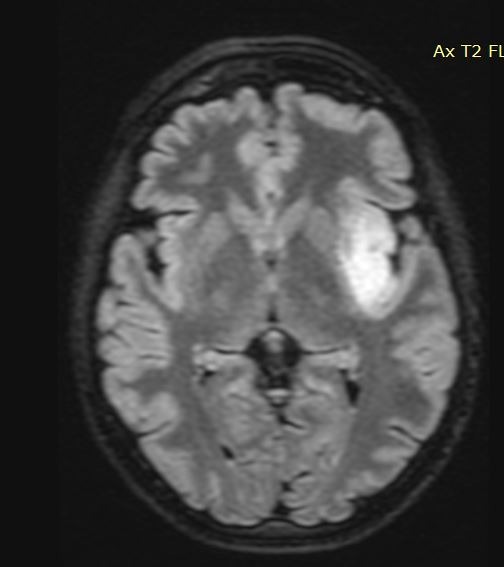

Γαγγλιογλοίωμα Ιπποκάμπου αριστερά

Ασθενής άνδρας, 38 ετών με πολλαπλά λιποθυμικά επεισόδια μετά από οσφρητική αύρα (επιληπτικές κρίσεις). Ο απεικονιστικός έλεγχος με μαγνητική τομογραφία ανέδειξε πάχυνση του αριστερού ιπποκάμπου